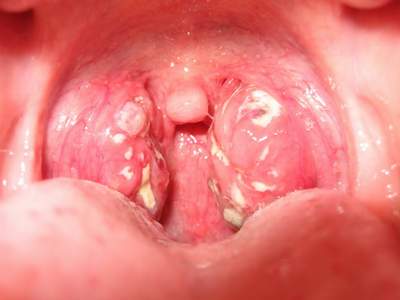

- Khi đi khám dễ dàng thấy được niêm mạc họng bị sưng, đỏ, có những chấm trắng, lớp mụn trắng trên bề mặt amidan